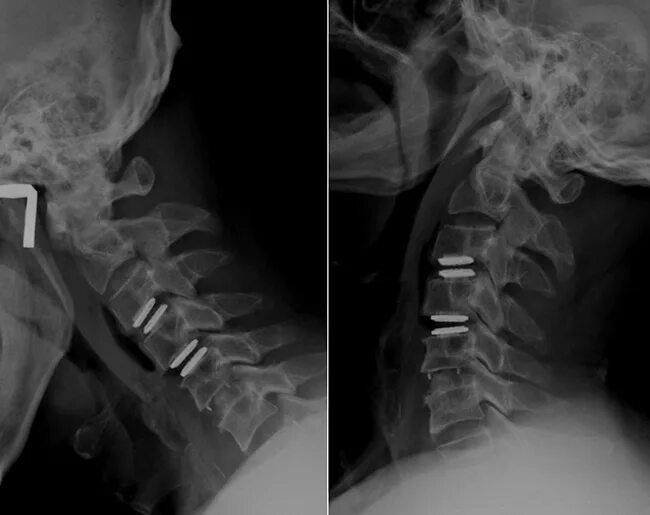

Грыжа с3